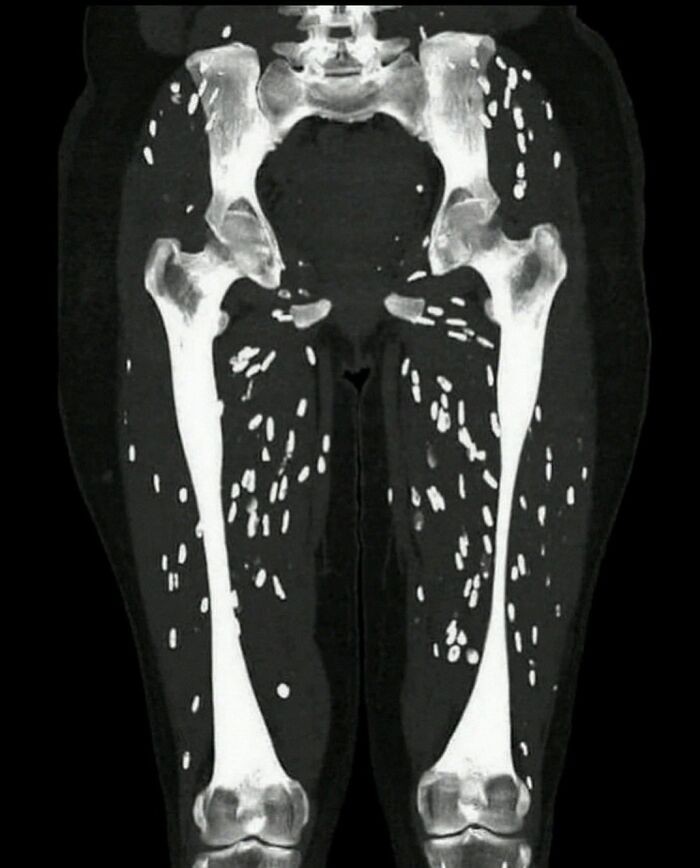

Fibrodysplasia ossificans progressiva adalah kelainan di mana jaringan otot dan jaringan ikat seperti tendon dan ligamen secara bertahap digantikan oleh tulang (mengalami osifikasi), membentuk tulang di luar kerangka (tulang ekstra-skeletal atau heterotopik) yang membatasi gerakan. Foto: Boredpanda

Pasien datang dengan keluhan kelemahan otot dan nyeri. Penyakit ini disebut sistiserkosis otot. Itu disebabkan oleh larva cacing pita di jaringan otot. Foto: Boredpanda